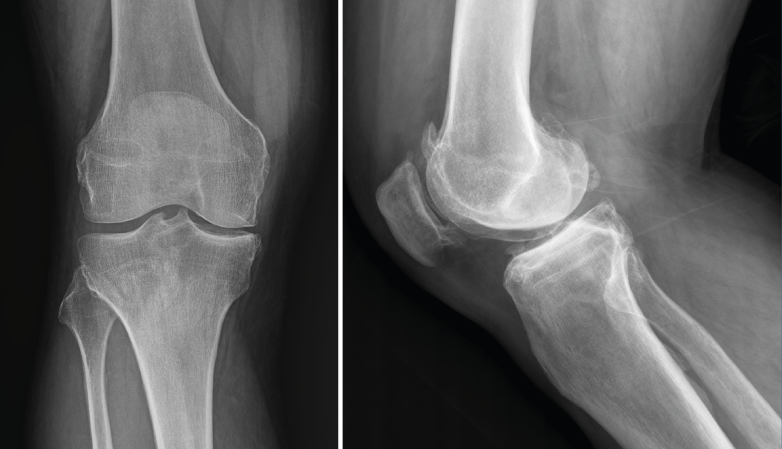

1.2. Luxación femorotibial

La luxación traumática de rodilla es una entidad poco frecuente, que representa menos del 0,5% del total de las luxaciones articulares(3).

Requiere un tratamiento precoz, ya que una de sus complicaciones más graves es la lesión de la arteria poplítea, para cuyo diagnóstico se recomienda realizar un estudio de angio-TAC (Figura 4).

Figura 4. Radiografías anteroposterior y lateral de rodilla: luxación anterior de tibia y peroné.